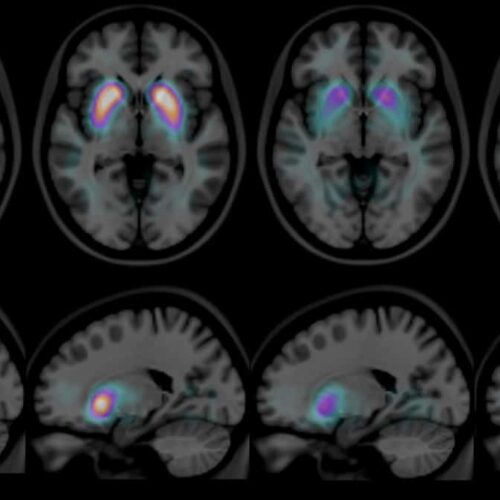

Situé au milieu du cerveau, ce petit organe fonctionne comme un chef d'orchestre qui contrôle toutes les glandes de votre corps. Votre médecin peut demander une IRM hypophysaire après certaines anomalies...